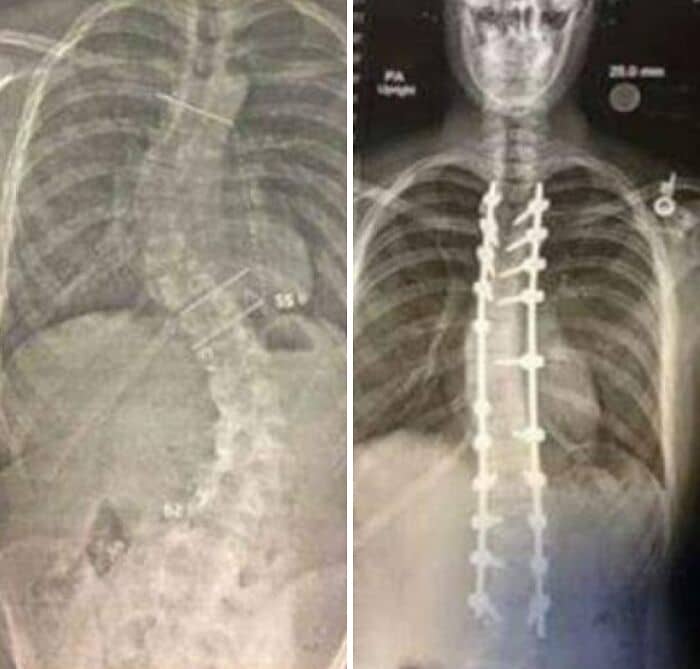

#10 These Are X-Rays Taken Before And After The Surgery

It has been 4 years to the day since I had my scoliosis surgery. The surgery itself took 14 hours. Surgeons drilled metal straightening bars into my spine.